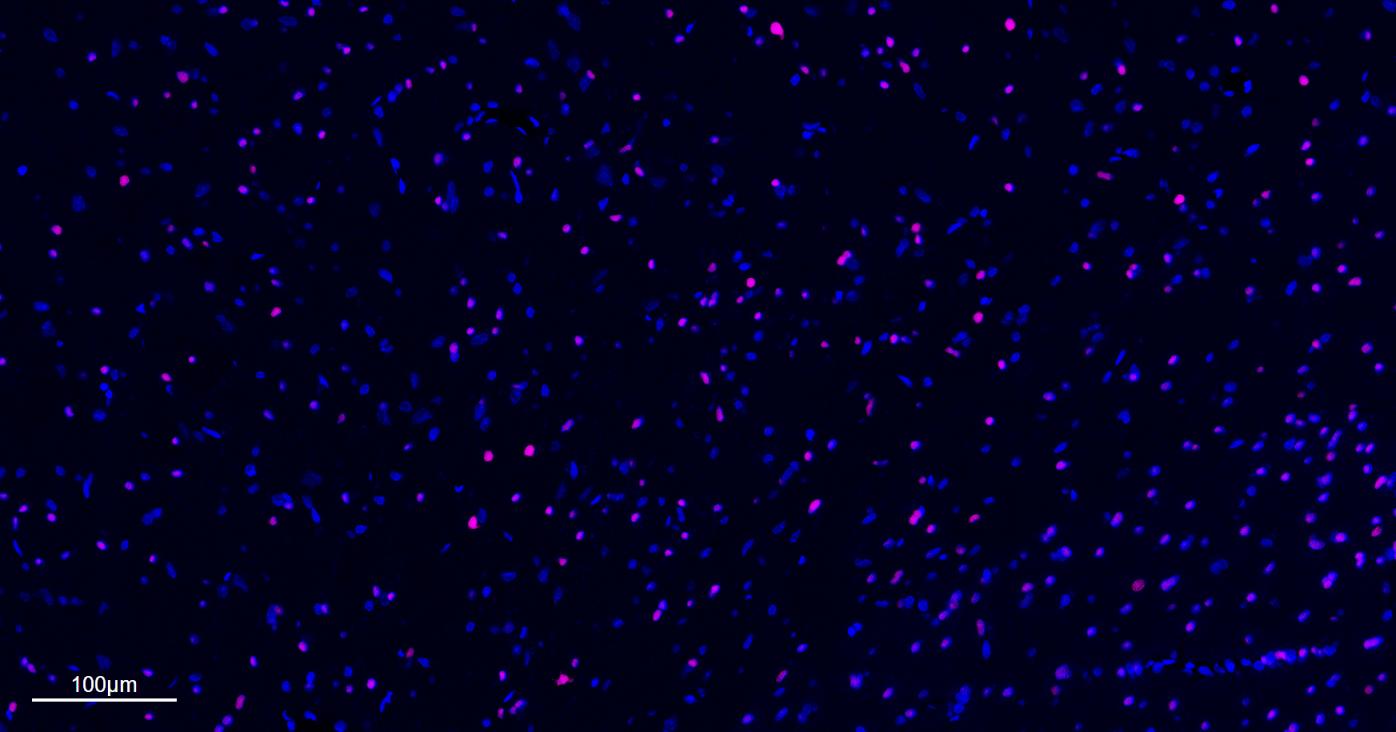

Paraformaldehyde-fixed, paraffin embedded Mouse Cerebrum; Antigen retrieval by boiling in sodium citrate buffer (pH6.0) for 15 min; The section was incubated with OLIG2 Monoclonal Antibody, Unconjugated (bsm-61115R) at 1:200 overnight at 4°C. Followed by conjugated Goat Anti-Rabbit IgG antibody (Rose pink, bs-0295G-BF647), DAPI (blue, C02-04002) was used to stain the cell nuclei.

Paraformaldehyde-fixed, paraffin embedded Human Cerebrum; Antigen retrieval by boiling in sodium citrate buffer (pH6.0) for 15 min; The section was incubated with OLIG2 Monoclonal Antibody, Unconjugated (bsm-61115R) at 1:200 overnight at 4°C. Followed by conjugated Goat Anti-Rabbit IgG antibody (Rose pink, bs-0295G-BF647), DAPI (blue, C02-04002) was used to stain the cell nuclei.

Paraformaldehyde-fixed, paraffin embedded Rat Cerebrum; Antigen retrieval by boiling in sodium citrate buffer (pH6.0) for 15 min; The section was incubated with OLIG2 Monoclonal Antibody, Unconjugated (bsm-61115R) at 1:200 overnight at 4°C. Followed by conjugated Goat Anti-Rabbit IgG antibody (Rose pink, bs-0295G-BF647), DAPI (blue, C02-04002) was used to stain the cell nuclei.